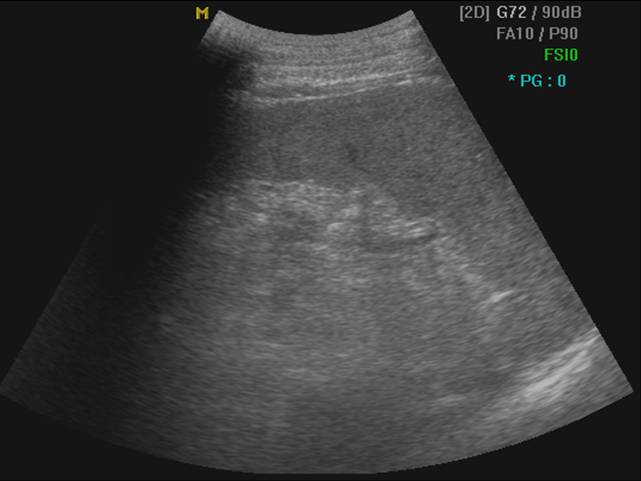

2 正常脾声像图